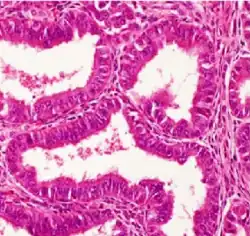

| Surface epithelial-stromal tumor | Serous tumor | 25% | 18.5% | Benign serous tumors of the right ovarian cyst are thinwalled unilocular cysts that are lined by ciliated pseudostratified cuboidal or columnar epithelium.[9] |

| Mucinous tumor | 15% | 8.8% | Benign mucinous tumors of the ovary consist of simple, nonstratified columnar epithelium with basally-located hyperchromatic nuclei and resemble gastric foveolar epithelium.[9] |

| Endometrioid tumor | 1% | Almost 100% | Tubular glands, resembling endometrium.[10] |